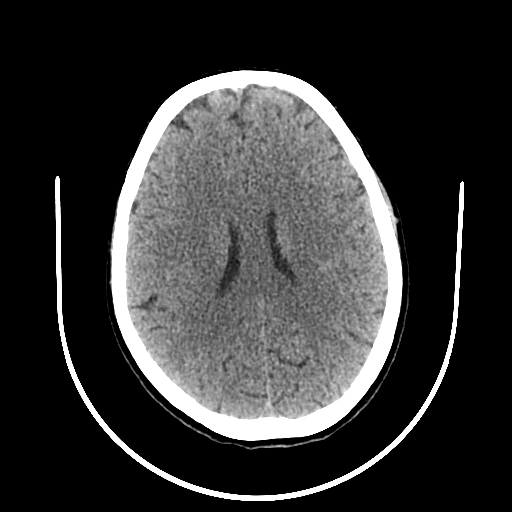

A 33 years old woman with protruding eyeballs & hyperthyroidism since 2 years